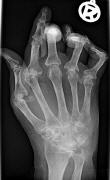

Gelenksschmerzen, juvenile Arthritis, Rheuma Arthritis, Rheuma de, Rheuma Ernährung, Rheuma in, Rheuma Medikamente Rheumatoide Arthritis lässt sich mit körpereigenen, gentechnisch veränderten Zellen dauerhaft lindern. Düsseldorfer Forscher haben es bewiesen.

Auch die rheumatoide Arthritis ist im Prinzip eine Erkrankung des Immunsystems. Dabei richtet sich die körpereigene Abwehr gegen den Körper selbst. Die äußerst schmerzhafte Folge sind geschwollene und entzündete Gelenke und zerstörtes Gelenkgewebe. Es gibt bislang keine Heilung. Schätzungsweise leidet rund eine Million Menschen in Deutschland an dieser Autoimmunkrankheit.

Arthritis, Arthritis Arthrose, Arthritis Behandlung, Arthritis bei, Arthritis Diagnose, Arthritis finger, Arthritis SymptomeDas Team um Studienleiter Peter Wehling spritzte körpereigene gentechnisch veränderte Zellen in betroffene Gelenke der Patientinnen. Diese Zellen stimulierten die Produktion eines Gegenspielers des Interleukin-1-Proteins, das für die Entzündungsprozesse verantwortlich ist. Der Antagonist sollte dessen Aktivität blockieren. Ziel der Aktion war, dass das veränderte Gen kontinuierlich innerhalb des Gelenks arbeiten sollte, um den schmerzhaften Zerstörungsprozess aufzuhalten.

Arthritis Therapie, Arthrose, Arthrose Behandlung, Arthritis, Arthritis Arthrose, Arthritis Behandlung, Arthritis bei, Arthritis DiagnoseVier Wochen nach der Zellinjektion berichteten die Patientinnen über verminderte Schmerzen und Schwellungen. Eine der beiden Probandinnen erlebte eine besonders große Wirkung: Das behandelte Gelenk blieb dauerhaft schmerzfrei, obwohl es in anderen Gelenken zu weiteren Rheumaschüben kam. Gewebeuntersuchungen aus dem behandelten Gelenk zeigten geringere Mengen des Interleukin-1-Proteins. Die Gentherapie hatte zu einer deutlichen Reduzierung des Entzündungsstoffs geführt. © Focus Online Gesundheit